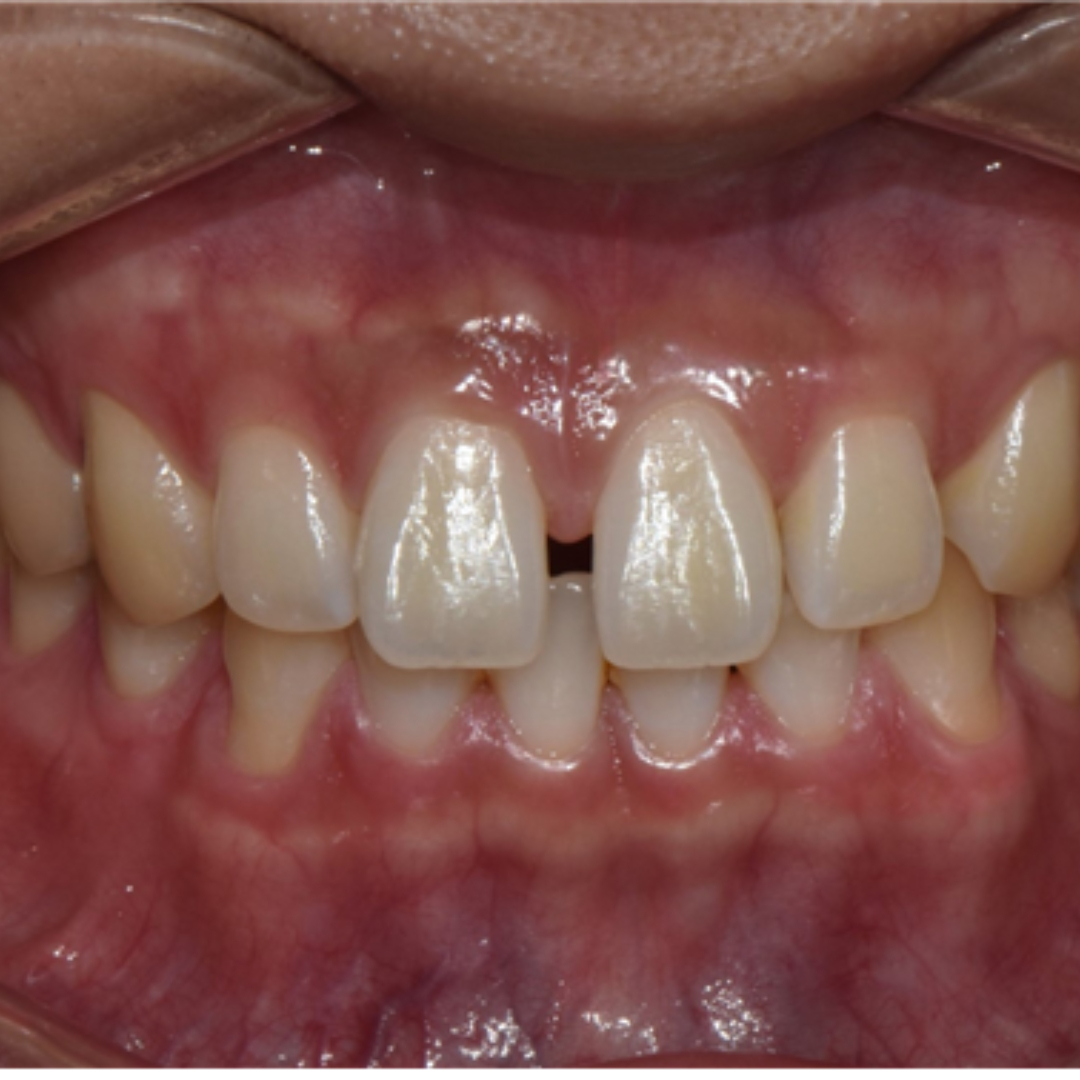

앞니 사이 벌어진 공간과 정중선 불일치를 고민으로 내원하셨던 20대 남성 환자분입니다. 윗니, 아랫니 공간이 각각 3.4mm, 2.6mm 가량 벌어져있고, 위와 아래의 중앙선 차이가 2.1mm 정도로, 상대적으로 정중이개와 정중선 불일치가 눈에 띄는 모습입니다. 해당 환자분께서는 격투기를 취미로 하시는 분이셔서 교정장치를 부착한 채로 얼굴 부위에 타격이 있을 경우 입 안이 다칠까봐 걱정이 있으셨습니다. 교정 진단 상담 후 고민 끝에 부상 방지를 위해 표면이 매끈한 투명교정 장치로 치료하시기로 결정하셨습니다.

치료 전, 후 미소가 눈에 띄게 개선되었습니다. 정면에서 두드러지게 보였던 정중 이개와 정중선 불일치가, 벌어진 공간이 폐쇄되고 가지런하게 배열되니 깔끔하고 정돈된 인상을 줍니다. 앞니의 벌어진 공간 폐쇄를 위해 라미네이트나 크라운 치료로 심미적이고 즉각적인 개선을 가져오는 경우도 있습니다. 하지만 위 환자분의 경우 다른 부정교합이 있기 때문에 교정 치료 없이 심미 보철을 진행했다면, 정중선 불일치가 잔존하거나, 앞니 크기가 비대칭적으로 마무리되었을 수 있습니다. 32주의 교정 치료로 자연스럽고 아름다운 미소를 회복하여 환자분도, 의료진도 만족한 결과를 얻어 성공적인 투명 교정 치료 증례로 소개드렸습니다. 세심한 진단과 맞춤형 치료계획으로 예쁜 미소를 찾아드립니다! 안전한 365서울앞선치과 교정 치료 많은 관심 부탁드립니다~!!

치료 전, 후 미소가 눈에 띄게 개선되었습니다. 정면에서 두드러지게 보였던 정중 이개와 정중선 불일치가, 벌어진 공간이 폐쇄되고 가지런하게 배열되니 깔끔하고 정돈된 인상을 줍니다. 앞니의 벌어진 공간 폐쇄를 위해 라미네이트나 크라운 치료로 심미적이고 즉각적인 개선을 가져오는 경우도 있습니다. 하지만 위 환자분의 경우 다른 부정교합이 있기 때문에 교정 치료 없이 심미 보철을 진행했다면, 정중선 불일치가 잔존하거나, 앞니 크기가 비대칭적으로 마무리되었을 수 있습니다. 32주의 교정 치료로 자연스럽고 아름다운 미소를 회복하여 환자분도, 의료진도 만족한 결과를 얻어 성공적인 투명 교정 치료 증례로 소개드렸습니다. 세심한 진단과 맞춤형 치료계획으로 예쁜 미소를 찾아드립니다! 안전한 365서울앞선치과 교정 치료 많은 관심 부탁드립니다~!! |